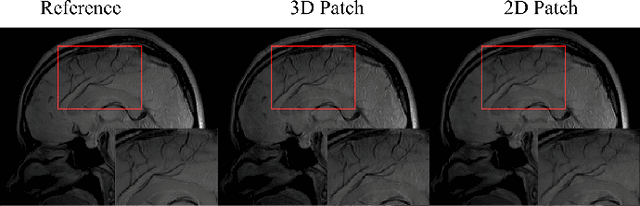

Abstract:Quantitative magnetic resonance (MR) parametric mapping is a promising approach for characterizing intrinsic tissue-dependent information. However, long scan time significantly hinders its widespread applications. Recently, low-rank tensor has been employed and demonstrated good performance in accelerating MR parametricmapping. In this study, we propose a novel method that uses spatial patch-based and parametric group-based low rank tensors simultaneously (SMART) to reconstruct images from highly undersampled k-space data. The spatial patch-based low-rank tensor exploits the high local and nonlocal redundancies and similarities between the contrast images in parametric mapping. The parametric group based low-rank tensor, which integrates similar exponential behavior of the image signals, is jointly used to enforce the multidimensional low-rankness in the reconstruction process. In vivo brain datasets were used to demonstrate the validity of the proposed method. Experimental results have demonstrated that the proposed method achieves 11.7-fold and 13.21-fold accelerations in two-dimensional and three-dimensional acquisitions, respectively, with more accurate reconstructed images and maps than several state-of-the-art methods. Prospective reconstruction results further demonstrate the capability of the SMART method in accelerating MR quantitative imaging.